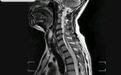

核磁共振

图1 :术前核磁共振检查:T1-11髓内可见条带状长T2信号影。椎管有效前后径在正常范围,椎管内未见占位征。T7-8椎板不连续,脊椎后软组织信号欠均匀。